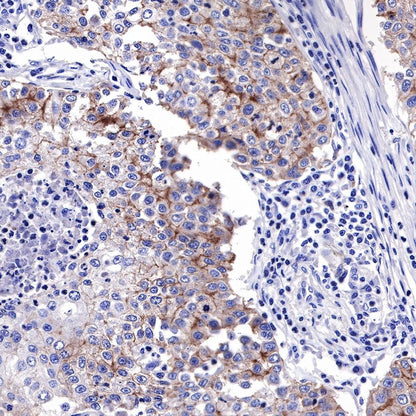

Immunohistochemistry

IHC shows positive staining in paraffin-embedded human endometrial cancer. Anti-EGFR antibody was used at 1/2000 dilution, followed by a HRP Polymer for Mouse & Rabbit IgG (ready to use). Counterstained with hematoxylin. Heat mediated antigen retrieval with Tris/EDTA buffer pH9.0 was performed before commencing with IHC staining protocol.